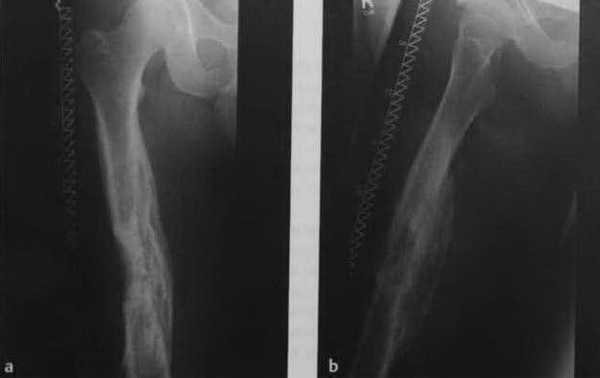

Рентгенограмма пациента с хроническим посттравматическим остеомиелитом, диагностированным 10 лет назад. Распространенные склеротические внутрикостные поражения и поражения надкостницы с увеличением рентгенопрозрачности, некоторые с нечеткими границами.